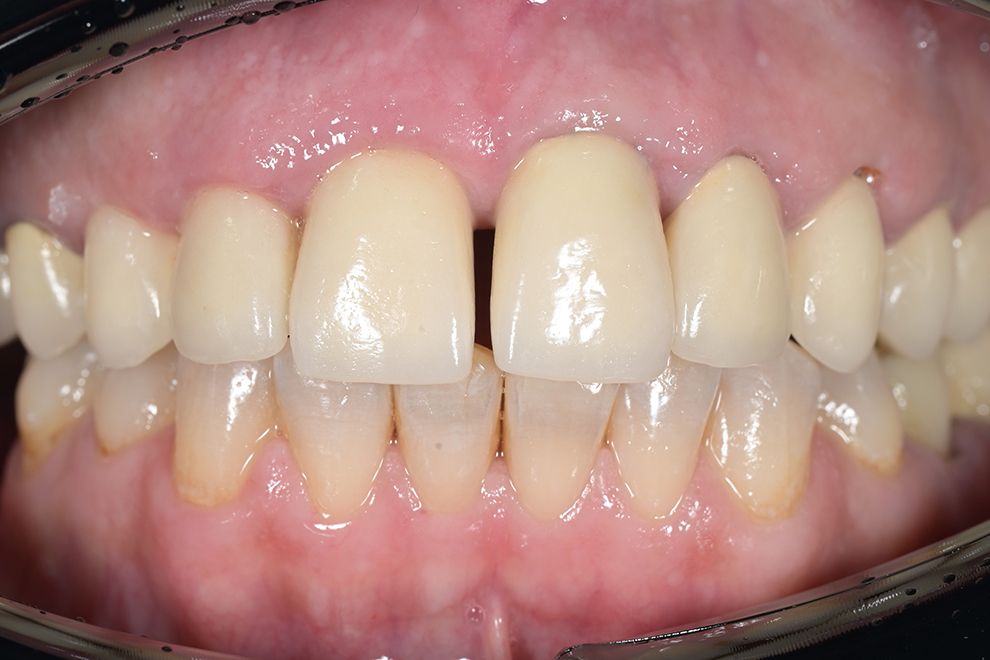

до и после